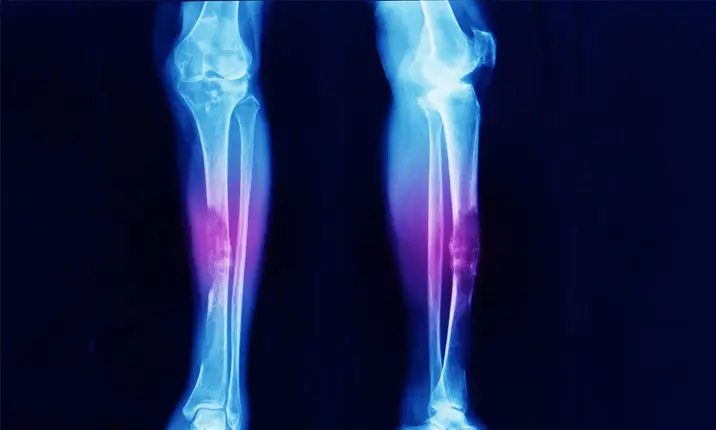

Sarcoma mô mềm là bệnh ung thư phát triển trong các mô mềm của cơ thể bạn như cơ, mỡ, gân hoặc sụn. Sarcoma mô mềm xảy ra phổ biến nhất ở các chi (cánh tay và chân của bạn). Bài viết này tìm hiểu kỹ hơn về sarcoma mô mềm ở chân và tay, các triệu chứng cần lưu ý và cách điều trị loại ung thư này.

Sarcoma mô mềm có thể phát triển trong cơ, các lớp sâu của da, trong mỡ, trong mạch máu, dây thần kinh và các mô liên kết khác. Mặc dù chúng có thể xuất hiện ở bất cứ đâu trên cơ thể nhưng hầu hết đều bắt đầu ở cánh tay và chân. Bài viết này sẽ tập trung vào việc điều trị sarcoma mô mềm ở cánh tay và chân.

Sarcoma mô mềm xuất hiện dưới dạng một khối u không đau, phát triển theo thời gian và có thể không được chú ý cho đến khi nó chèn ép lên cơ hoặc dây thần kinh. Hãy đi khám bác sĩ nếu xuất hiện khối u đang phát triển hoặc gây đau.